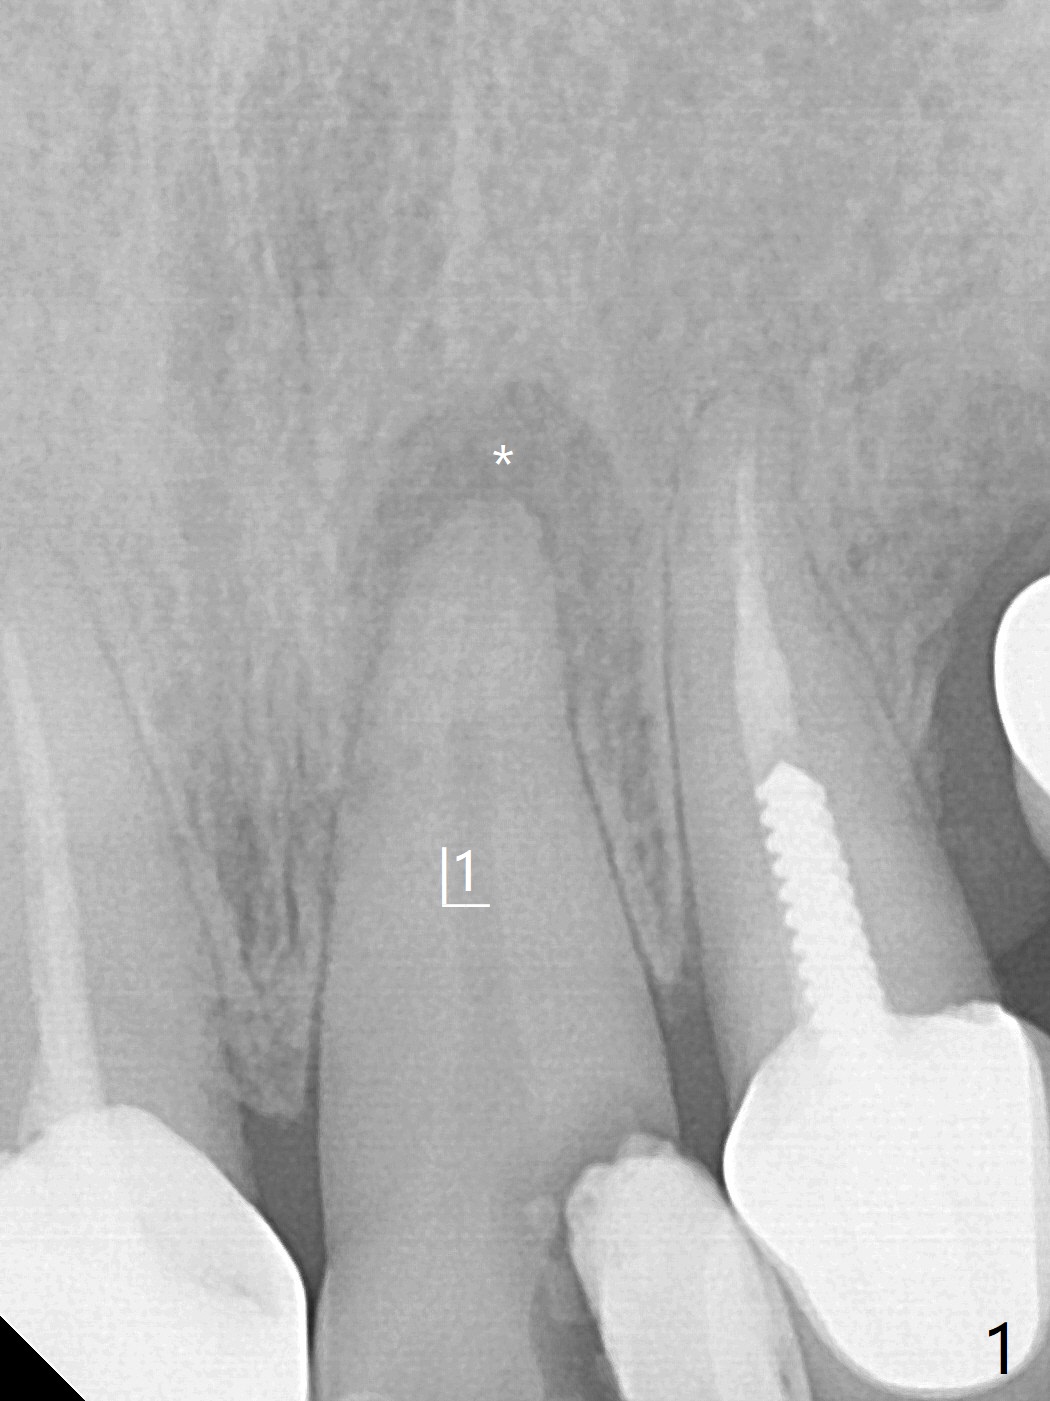

62岁女因牙痛(图一)做根管治疗(图二,三)。一年10个月后因11,13,30,31 植牙,拍摄CT,根尖阴影明显缩小(图四,五)。颊侧骨板薄而短(图四:>),牙槽骨也狭窄,如果需要植牙,比较困难。